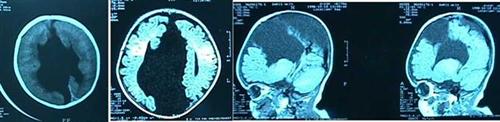

* İki yarı-beyin küresi arasındaki (interhemisferik) araknoid kistler

Bunlar çok sık görülmez. Beraberinde beyinde bazı gelişim bozuklukları olabilir (Resim 13). En sık görülen gelişim bozukluğu heri iki beyin yarı-küresi arasındaki bilgilerin birbirine iletilmesine yarayan köprü organ korpus kallozumun gelişmemesidir. Şant ve açık cerrahi tedavi yöntemi olarak uygulanmaktadır. Karıncıklar ile kist arasında ince bir duvar var ise endoskopik olarak kist karıncığa ağızlaştırılabilir.

Resim 13: BT ve MRG kesitlerinde İki yarı-beyin küresi arasındaki (interhemisferik) araknoid kist izlenmektedir.